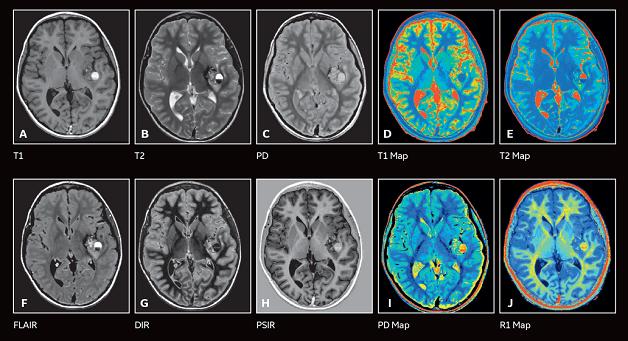

Hình ảnh chụp MRI giúp bác sĩ chẩn đoán được nhiều bệnh lý